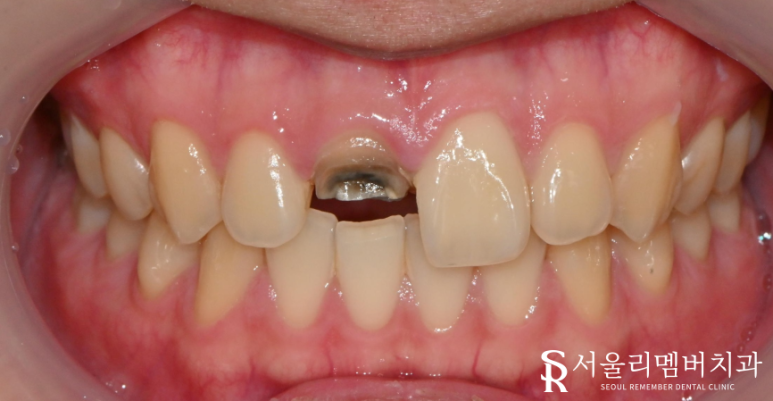

구강 사진입니다.

신경치료를 받은 치아는 충치가 생겨도 통증이나

증상이 없기 때문에 알기 쉽지 않습니다.

정기 검진을 받으며 계속 체크해 주셔야 합니다.

크라운 내부에 충치가 생긴것을 모르고 계시다

시간이 지나 더 이상 버티지 못하고 부러진 것입니다.

이런 경우 치관이 많이 남아있지 않아

재 신경치료 후에 기둥을 심어 보강 해주어야 합니다.